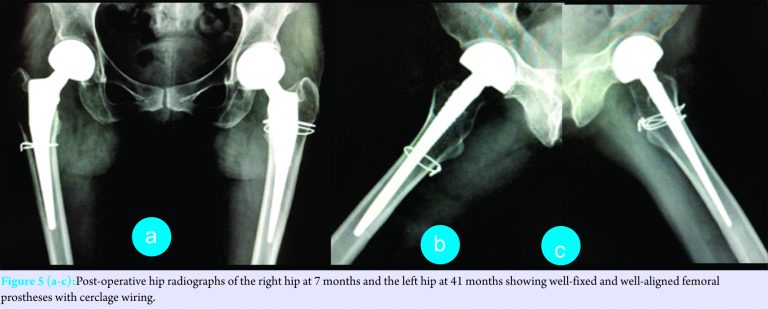

Case Report: We report the case of a 46-year-old Thai female who presented with consecutive bilateral femoral neck fractures following minor trauma within a 3-year period and received cementless bipolar hemiarthroplasties. Her phenotypic expression included Achilles tendon masses, childhood-onset cataracts, intellectual disability, and cerebellar ataxia. A brain computed tomography showed non-enhancing hypodense lesions in the bilateral cerebellar hemispheres with mild brain atrophy. Histopathology from an Achilles tendon biopsy revealed tendinous xanthoma and molecular analysis confirmed a homozygous nonsense mutation, c.1072C>T (p.Gln358Ter), in exon 6 of the CYP27A1 gene. The intra-operative crack of a calcar femorale was a major complication during both prosthetic insertion surgeries and warranted cerclage wiring. At the 7-month follow-up of the right hip and the 41-month follow-up of the left hip, postoperative radiographs showed well-fixed and well-aligned prostheses. Independent household ambulation could be resumed with Harris hip scores of 81 points equally.

She was prescribed oral calcium carbonate with Vitamin D2 for osteoporotic prophylaxis and allowed partial weight bearing for 6 weeks. The hip radiographs at the latest follow-up (post-operative 7 and 41 months for right and left hips, respectively) showed well-fixed and well-aligned femoral prostheses (Fig. 5a-c).The right leg was found to be 5 mm shorter. A CT scan of both hips and femurs demonstrated 12° and 15° anteversion of right and left femoral stems, respectively. The native acetabular anteversion was 23°. She occasionally had slight pain in both hips but no compromise in activity. She could stand without support and walk with a slight limp for 10–15 minutes. She was capable of going up or down stairs with handrails. Both hip joints had a full range of movement with Harris hip scores of 81 points equally.